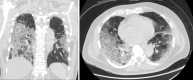

Figure 2

CT scan of the chest showing COVID-19 pneumonia during initial presentation to the hospital. The CT was negative for any mediastinal pathology. Note the extensive bilateral ground-glass infiltrates.